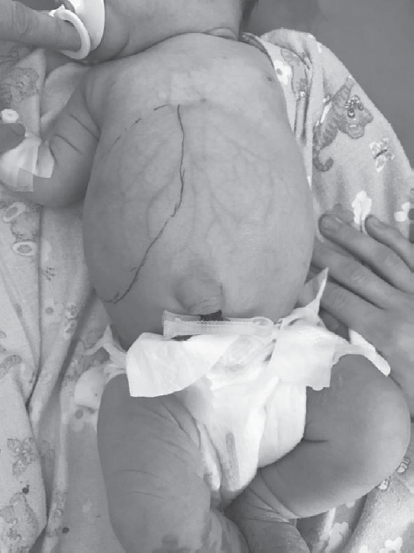

Гемангиомы — наиболее часто встречающиеся доброкачественные сосудистые образования печени детского возраста, которые могут приобретать как злокачественное течение, так и спонтанно регрессировать. На первом году жизни их распространенность составляет 10–12 %. Среди недоношенных детей распространенность гемангиом коррелирует со степенью недоношенности. Гемангиомы небольших размеров, как правило, не требуют специфического лечения и протекают бессимптомно. Образования крупных размеров могут вызывать жизнеугрожающие состояния: тяжелую тромбоцитопению с коагулопатией (синдром Казабаха – Меррита), анемию, кровоизлияние в опухоль, спонтанные и травматические разрывы опухоли, сердечную недостаточность, связанную с внутриопухолевым шунтированием кровотока, синдром абдоминальной компрессии, тяжелый гипотиреоз. Диагноз устанавливается на основании совокупности данных медицинской визуализации, лабораторной диагностики и клинической картины. В данном обзоре представлены ключевые моменты общей классификации, наиболее характерные диагностические признаки, а также базовые алгоритмы лечения гемангиом печени у новорожденных и детей первого года жизни. Также описаны 2 клинических случая новорожденных с гигантскими гемангиомами печени, которые обследовались и получали лечение в отделении патологии новорожденных и детей грудного возраста Перинатального центра Санкт-Петербургского государственного педиатрического медицинского университета с описанием особенностей течения каждого из них.